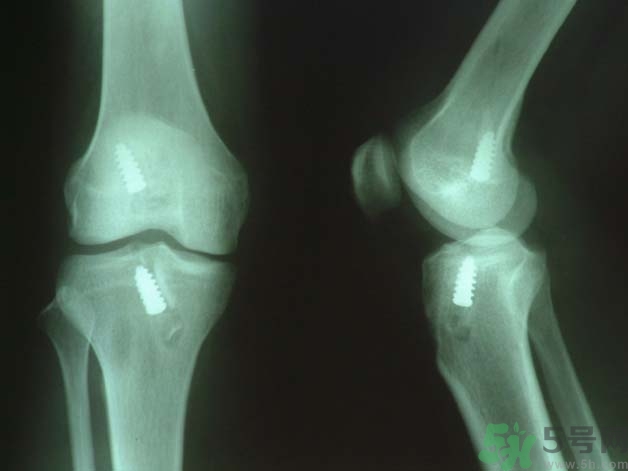

原則上應行手術治療如韌帶斷裂,可直接縫合;如骨附著處撕脫,可用鋼絲貫穿法固定或直接縫合于骨膜及軟組織上。如有撕脫骨片,則用鋼絲或螺絲釘固定。如合并半月軟骨損傷,應予以切除。合并前膝交叉韌帶損傷者,應先修補。術后石膏固定4—6周。

前交叉韌帶合并脛骨棘撕脫骨折者,可用膝過伸和后推脛骨使之復位,用長腿石膏固定4—6周。對于未能復位者,應及時手術修補。將骨折片用鋼絲固定。單純韌帶斷裂者,用石膏固定。對陳舊性損傷,以保守治療為主,經(jīng)鍛煉后,關節(jié)仍不穩(wěn)定,亦可考慮手術修補。后交叉韌帶可不修補。